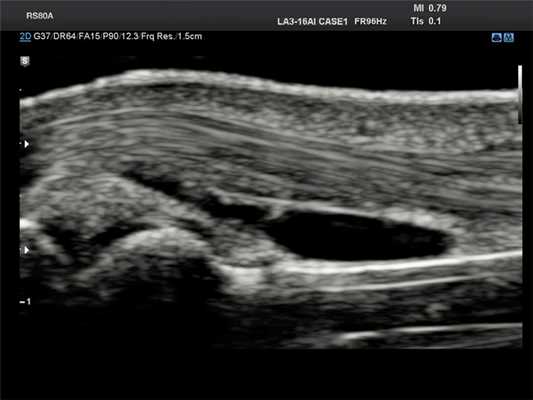

На УЗИ ганглий выглядит как одно- или многокамерное образование с тонким «ободком» и множественными перегородками, чаще всего анэхогенное, реже с эхогенными включениями. Может обнаруживаться также акустическое усиление. Для поиска кровотока в образовании и признаков, позволяющих отличить ганглий от опухоли, используется цветовая или энергетическая допплерография. Ультрасонография, допплерография, МРТ — наилучшие методы визуализации сухожильного ганглия.

Палец - сухожильный ганглий, B-режим

[EN] Эхограмма №685: Сухожильный ганглий на пальце в B-режиме.

Изображение получено с помощью УЗ сканера RS80 (есть в продаже).